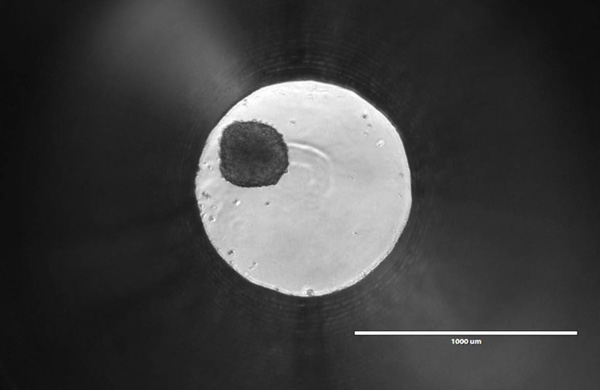

There’s something beautiful about the tiny ball I’m looking at through the microscope. It’s only about 200—250 microns in diameter, smaller than a single grain of salt. As I bump the plate with my finger, the ball rolls around the 1mm well. To me, it may just look like a dark spot within an illuminated circle, but many scientists feel it could represent the future of oncology research and drug discovery.

It’s a Friday afternoon, and I’m staring at a spheroid of roughly 1,000 human liver cells. Promega Research Scientist Mike Valley heard that I was interested in 3-dimensional cell culture models, so he invited me over to his lab in the Research and Development Center to check out the spheroids for myself. Mike is developing a new assay, and with recent trends in cell biology research, he knows it’s crucial to optimize that assay for use with 3D cultures.

In 2D culture, cells are typically plated in a flat monolayer. One-sided attachment induces a polarity that is unnatural for many cells. It also means that each cell is getting equal access to nutrients and oxygen, resulting in uniform growth and proliferation. Each cell is likely at the same metabolic state, which is rare in the body. Tumors, in contrast, show high levels of heterogeneity, with some cells actively proliferating, others quiescent, and some necrotic. This issue is less prevalent in 3D spheroids, where nutrient gradients emerge gradually as the diameter increases. As the spheroid grows, the cells in the core begin to experience reduced oxygen exposure. This results in a hypoxia gradient, which can lead inner layers to quiescence and even necrosis.

Image credits: Spheroid image provided by Insphero, all other photographs by Wesley Bishop.